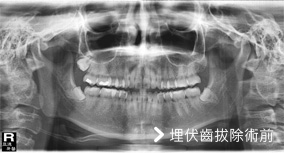

埋伏齒拔除

此為埋伏齒手術前後對照照片,照片的左邊其實是病人的右邊。從照片上可以看到左右下牙床智齒成水平狀態,屬於難度高的手術,需開刀拔除。

埋伏齒疼痛度高於其它牙齒問題,有時會造成牙齦會腫,面頰會腫,嘴巴無法張開等問題,一般而言,矯正醫師會在矯正前要求病人拔除埋伏齒,使矯正治療順利進行。

原本矯正好或是原本就很好的齒列,會因為埋伏齒生長,使齒列改變為不齊,影響美觀。大部分病患罹患埋伏齒疼痛,診所醫生都轉診大醫院,原因是:診所設備不足,拔除困難,手術時間長,術後易流血和感染,醫生相對承受風險大。